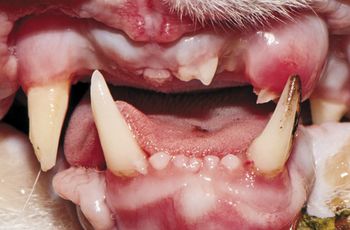

DEK Bulldogs, Labrador retrievers and beagles are prone to it. Why, what is it, and what can be done?